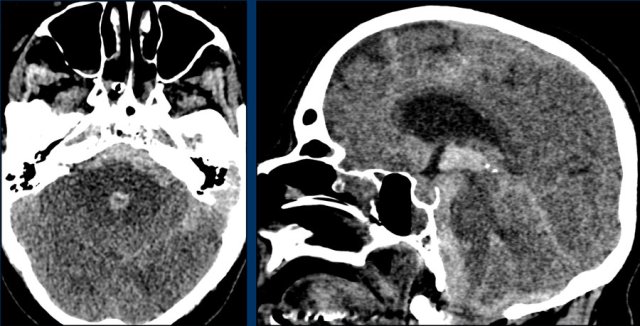

Cerebellar

This patient presented with a cerebellar hemorrhage.

The gradient echo-images show multiple microbleeds.

This can be the result of long standing hypertension due to the central location of some of the microbleeds.

This patient presented with a cerebellar hematoma.

Continue with the T1W-image...

The T1W-image shows a hyperintense hemorrhage (arrow).